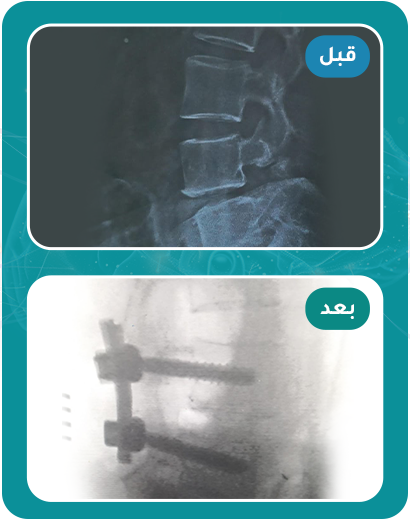

قصص مرضى تغيرت حياتهم للأفضل بعد العلاج